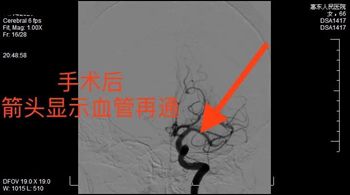

对于这类手术早已驾轻就熟的卒中团队,井然有序、娴熟配合,大大缩短了手术时间,取栓导管在最短时间内精准到达血栓点,并成功取出长约5cm的血栓。经再一次造影显示左侧大脑中动脉及其分支血流通畅,复查头颅CT 无术后出血。标志着此次手术妥善完成。

术前图                                                                 术后

患者术后恢复良好,从手术前右侧肢体不能抬举(1级肌力)恢复至右侧肢体可抬举活动(4级肌力)。